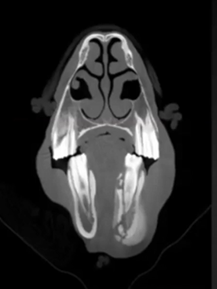

Read MoreThis horse has all the clinical symptoms of periodontal disease. CT images show an increase in periodontal ligament width, horizontal/vertical bone loss, periodontal infection, diastema, food impaction causing infection to spread and creation of a draining tract.

Featured: Travis Henry, University of Wisconsin-Madison